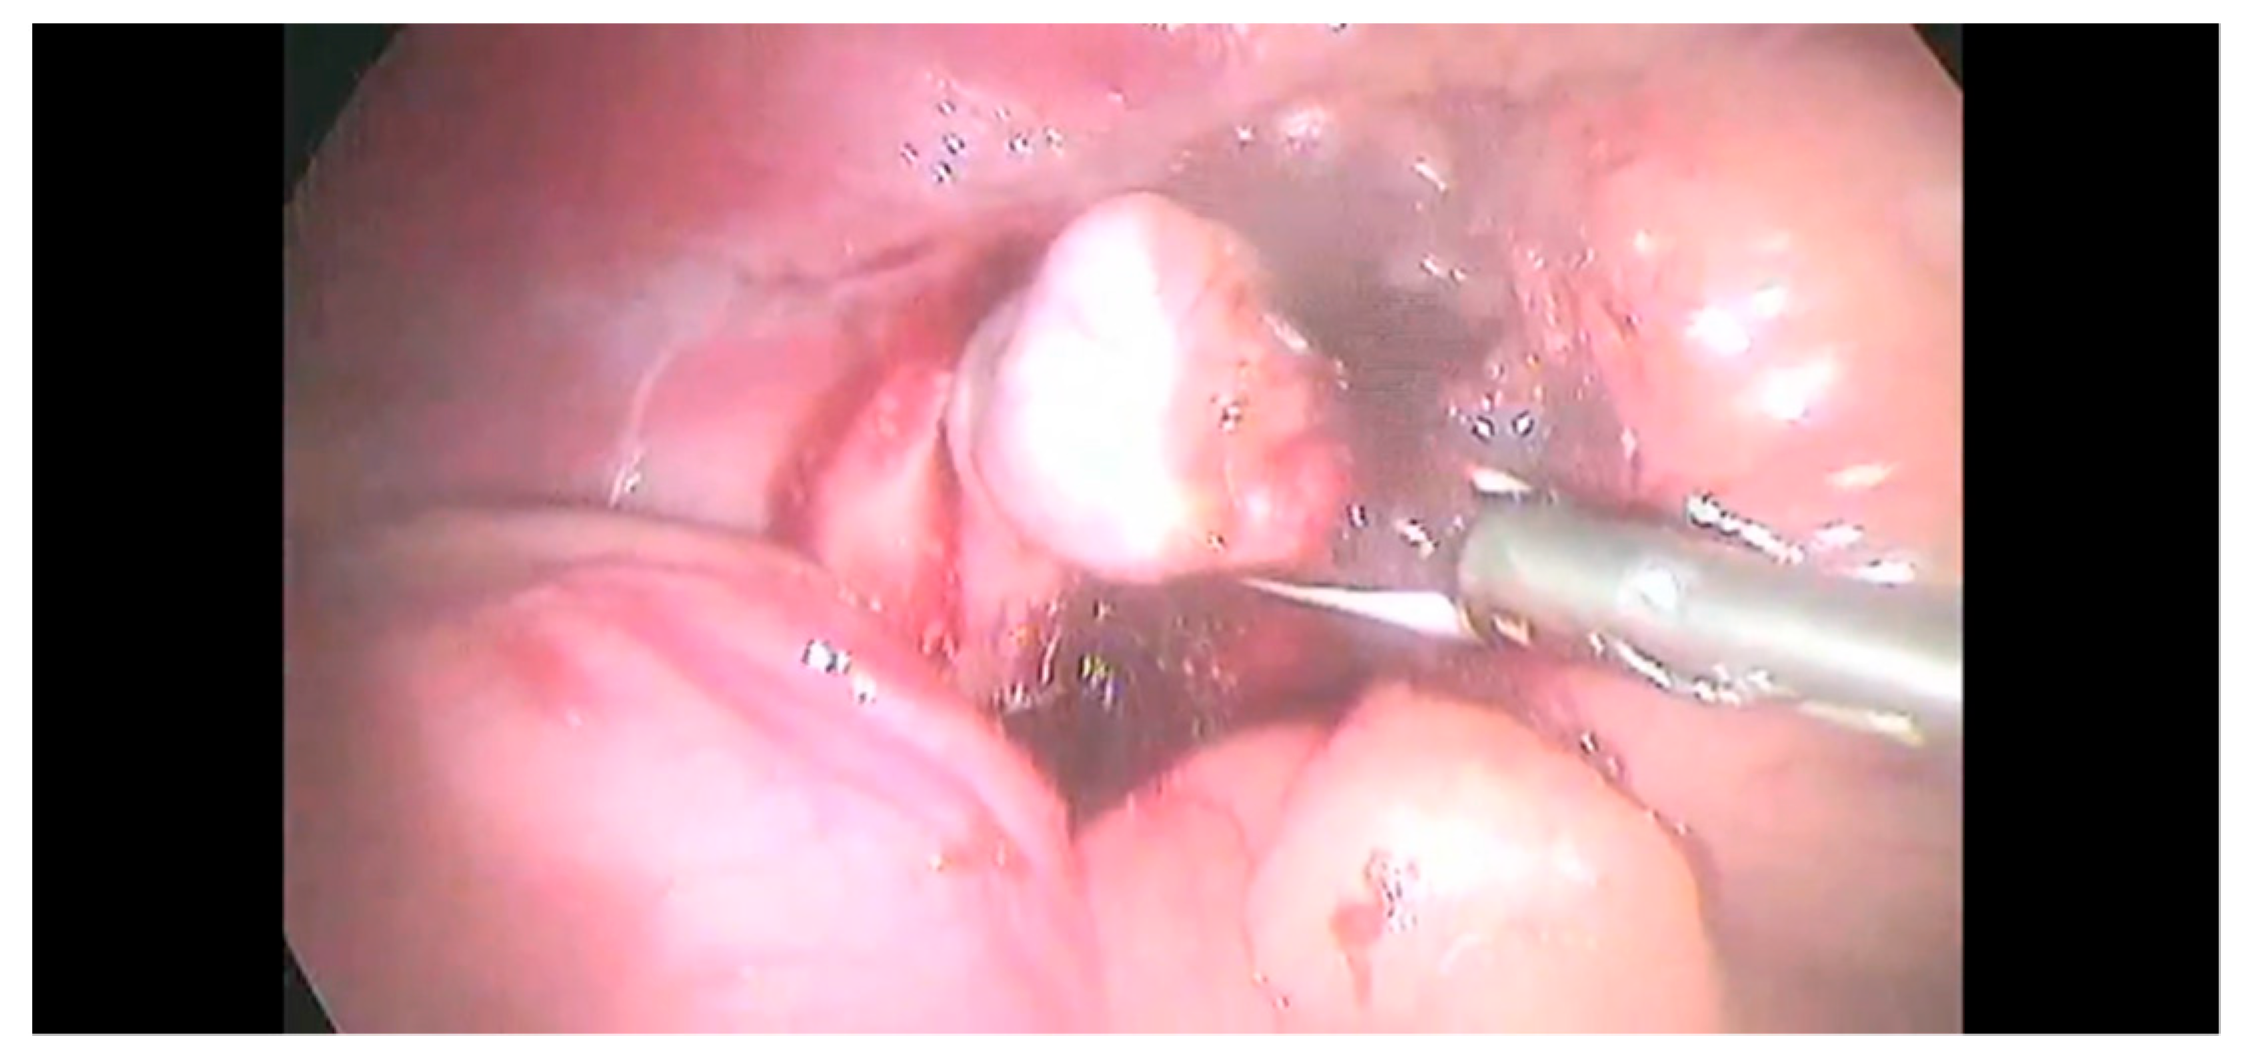

On the left side, the dissection started with the blunt incision of the peritoneum over the caudal margin of the tumor using the Kelly forceps or, alternatively, the tip of a vessel sealer. The dissection was continued cranially until the phrenicoabdominal vessel was evident, then, it was sealed and sectioned with LigaSure™ (Figure 4); however, laparoscopic hemoclips (Endo clip II ML, Tyco Health- care, Milano, Italy) were sometimes used in addition to the vessel-sealing device.

Figure 4.

The phrenicoabdominal (PA) vein and artery were identified and sealed using a sealing device.